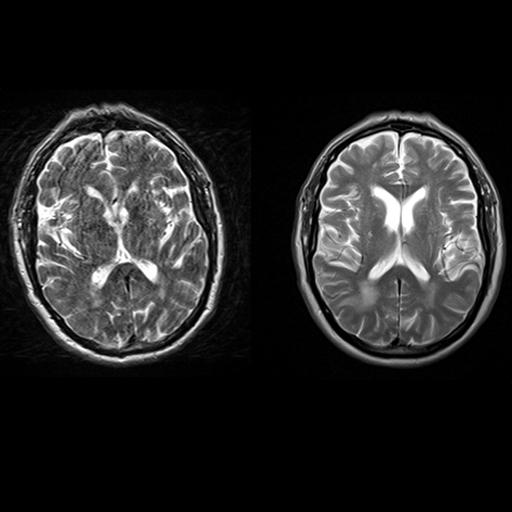

| Axial T2w TSE images of the brain (left: without

motion correction; right: with syngo BLADE) |

Axial T2w TSE images of the brain (left: without

Sagittal T2w TSE images of the brain (left:

without motion correction; right: with syngo BLADE) |

Coronal T2w TSE images of the brain (left: